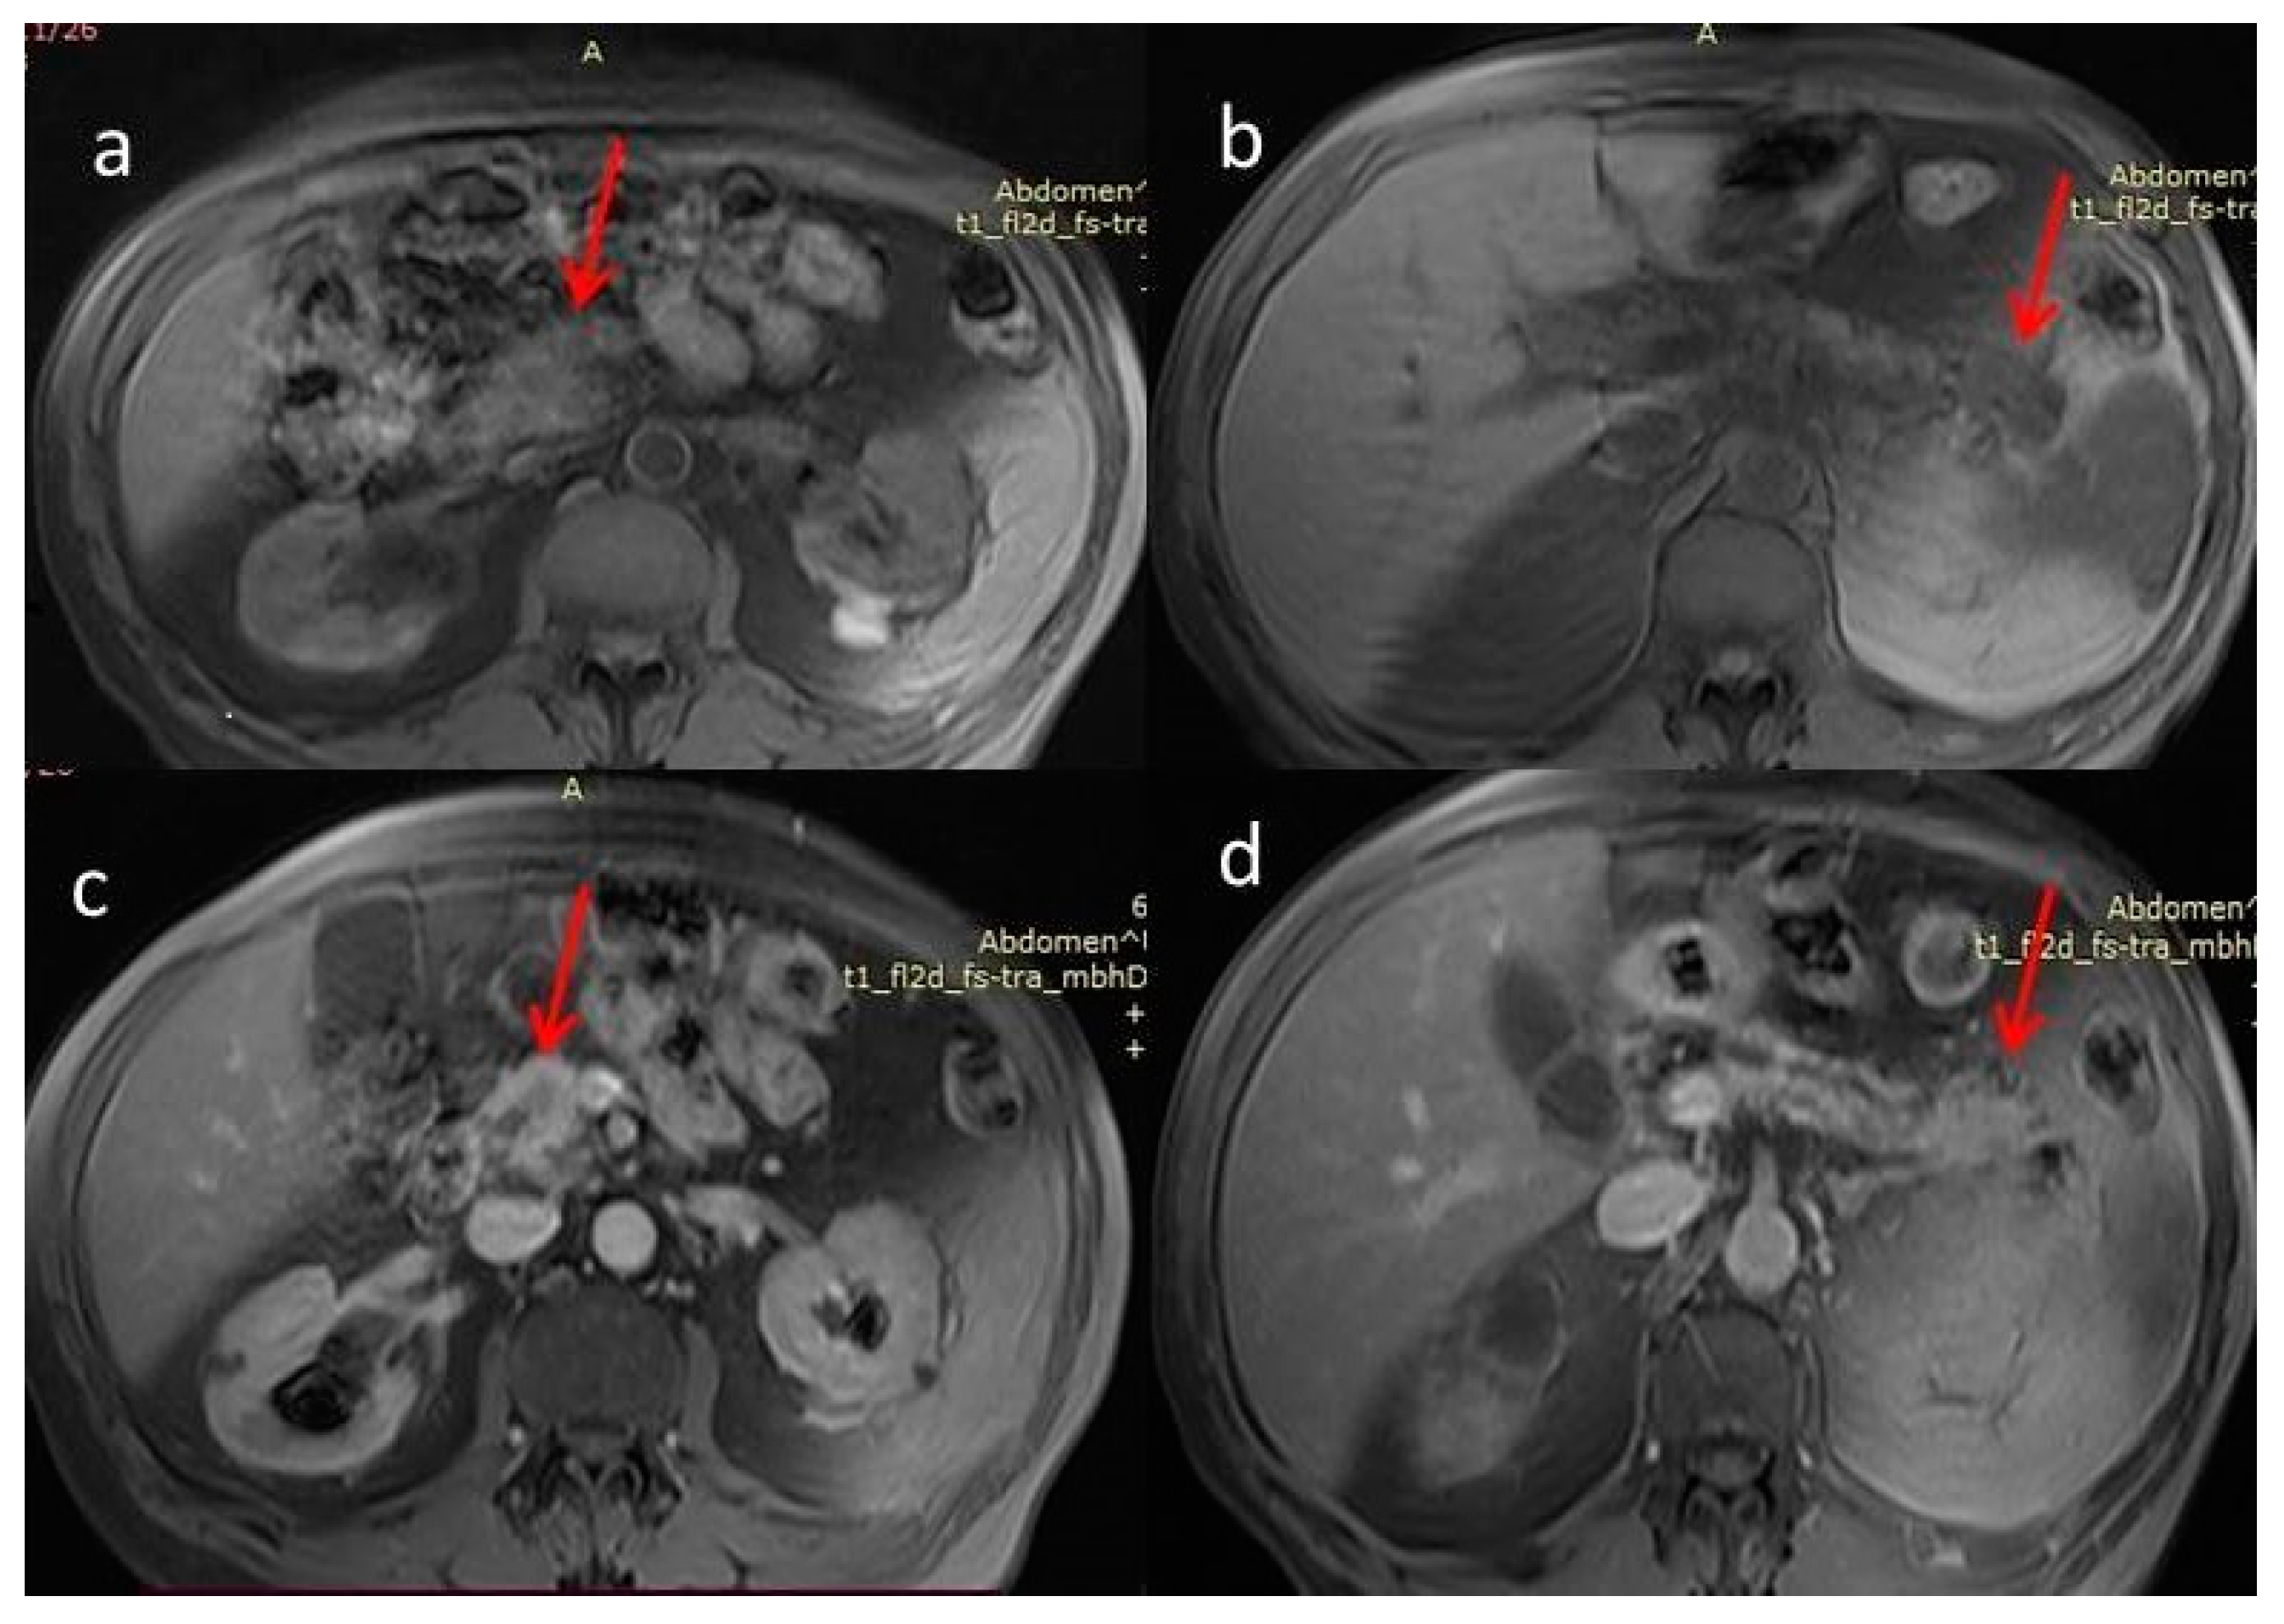

2. Case Report